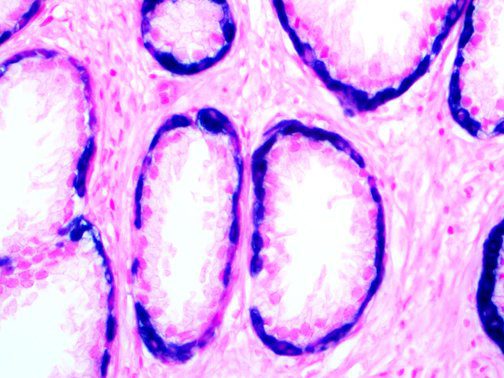

The first cytokines released are interleukin 1β (IL-1β) and tumor necrosis factor-α (TNF-α), which attract a variety of circulating white blood cells (WBCs) to the infection site, including neutrophils, monocytes, macrophages, and natural killer (NK) cells. This response, along with the antipathogenic chemicals released by these cells (i.e., complement), comprise the innate immune response. These cells directly attack the invading pathogen and also release additional cytokines, chief among them interleukin-1 and 6 (IL-6). IL-6 is essential for invoking the adaptive immune response, which calls T-cells, B-cells, and T helper (Th) cells to the infection site. IL-6 also stimulates further recruitment, proliferation and activation of macrophages.

This activation induces inflammatory monocytes to highly express IL-6, starting a localized and then systemic cascade effect that results in hyperproduction of IL-6, which accelerates the inflammatory process. Because IL-6 also increases vascular permeability, excessive levels cause blood vessels to become very leaky. This, along with clotting factors released from vascular endothelial cells, stimulates the coagulation cascade, resulting in microthrombosis (tiny clots), which leads to ischemia and tissue death of the kidney, intestines, heart, liver, brain and extremities.